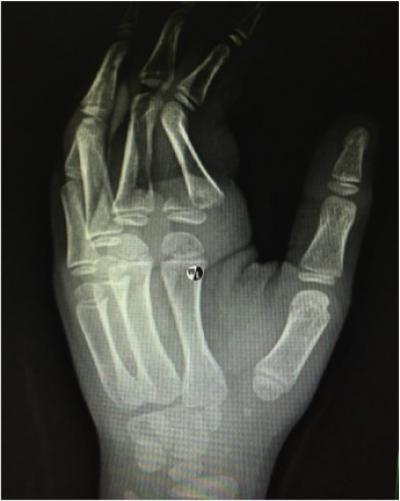

Adhesions as an Uncommon Complication of K-wiring

Nanchappan S

,

Parminder GS

Nur Azuatul AK

Tan JA

Ahmad Suparno B

Jamari S

Shalimar A

Related Terms:

adhesions

flexor tendon

fracture

percutaneous K–wire

phalanx

proximal

Case report